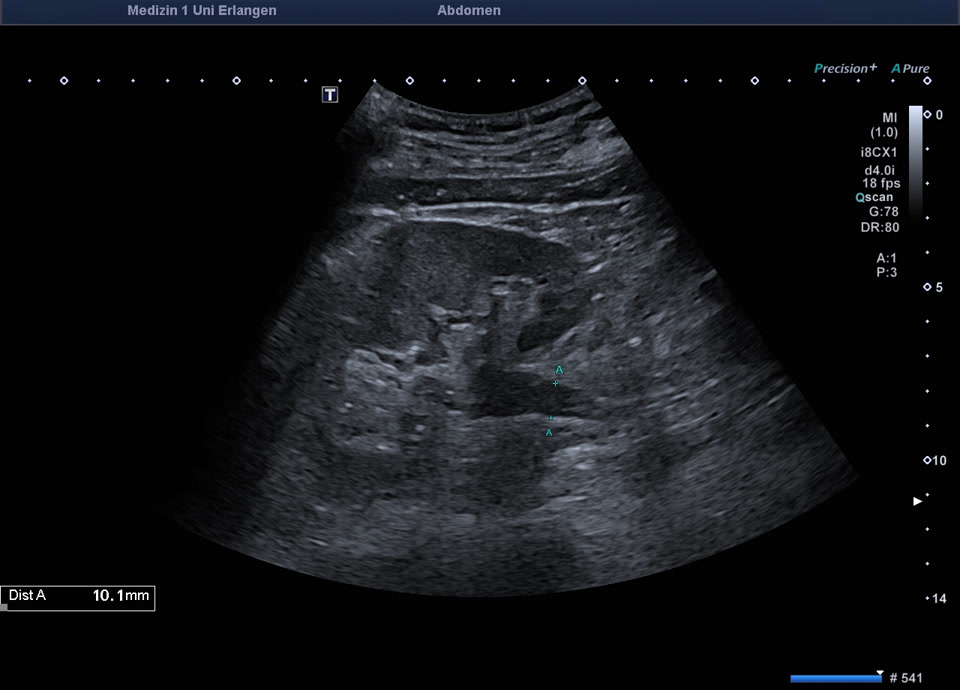

83 jährige Patientin mit Harnstau I° bei liegender Uretherschiene bei 11 cm großer retroperitonealer Raumforderung im linken Mittelbach (DD Lymphom)